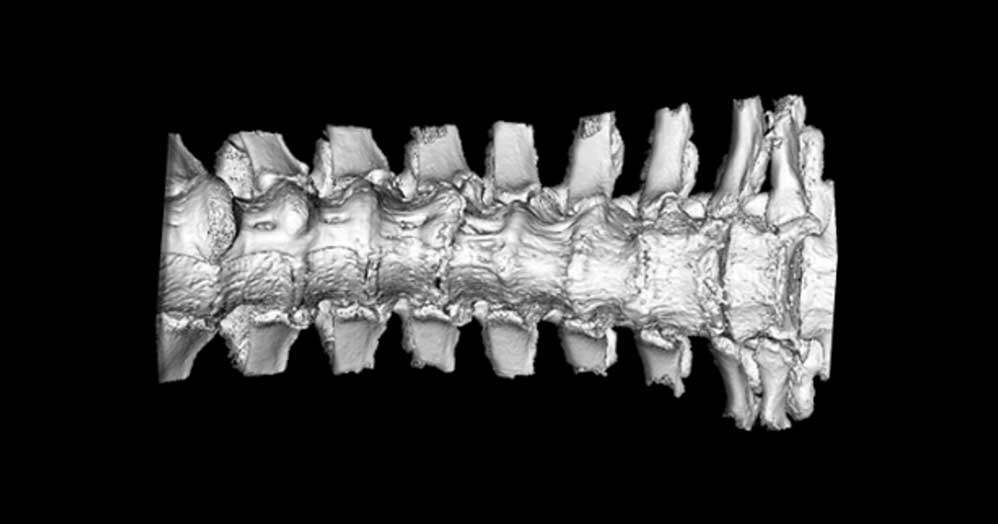

Prior studies suggest DISH affects up to a third of men over the age of 50. This non-inflammatory type of arthritis is characterized by the progressive calcification of spinal tissues that eventually leads to the fusion of the vertebrae within the spine. However, whether this calcification causes pain, especially in the early stages of the disease, isn’t well understood or well documented.

Using a mouse model, the team demonstrated in a study recently published in the journal Arthritis Research & Therapy that even in the early stages of the disease, there was evidence of back stiffness and pain.

These results are the first evidence of impaired physical function, axial stiffness and pain associated with spine calcification in mice. The researchers say it underscores the need for pain to be evaluated in people living with DISH through the progression of spine calcification, with emphasis on the early stages of the disease.

To complicate matters further, the spine calcification associated with DISH occurs progressively over an extended period of time, often beginning decades before a person is diagnosed.